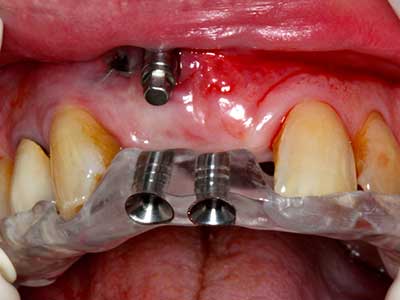

Abb. 14: Einbringung von vier konischen RSX-Implantaten (Bego Implant Systems, Bremen).

Abb. 15: Die röntgenologische Ein-Jahres-Kontrolle zeigt stabile Verhältnisse des Knochenniveaus.

Abb. 16: Auch intraoral stabile Verhältnisse mit Einbettung der Implantate in keratinisierter Gingiva.